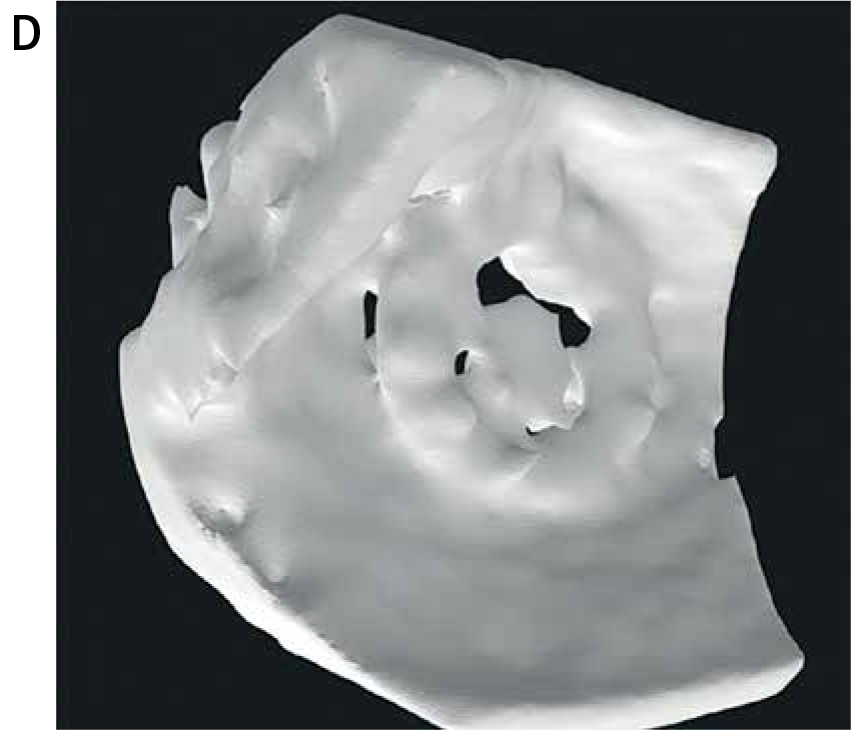

Zespół z GCM i ŚUM wykorzystał dane z echokardiografii 3D-TEE, które po konwersji do plików 3D, dzięki segmentacji w oprogramowaniu powiązanym z drukarką 3D (slicer), zostały wydrukowane w rzeczywistej skali na drukarce Stratasys Objet 30 (v.3) w technologii PolyJet.

Do druku modeli użyto materiałów sztywnych (IORA Model i IORA Support dla koniecznych w pracy drukarki podpór, oba firmy Isquared). Na drukarce Objet 30 uzyskać można wysoką dokładność odwzorowania struktur anatomicznych z odchyleniem nieprzekraczającym ±100 μm przy modelach poniżej 100 mm długości.

W projekcie przeanalizowano 8 przypadków pacjentów z PVL w mitralnych zastawkach mechanicznych lub biologicznych. W testach symulacyjnych przeprowadzonych na wydrukowanych modelach, dobrano optymalne rozmiary okluderów, co później porównano z rzeczywistym postępowaniem klinicznym.

W 7 z 8 przypadków dobór okludera na podstawie wydrukowanego modelu pokrywał się z decyzją podjętą w trakcie rzeczywistego zabiegu. W jednym przypadku konieczna była zmiana strategii, jednak model także wskazywał taką możliwość jako jedną z alternatyw.

- Modele drukowano w skali 1:1

- Wydrukowano z materiału sztywnego, przezroczystego

- Przykładowe rozmiary okluderów: PLD-W – 12×5 mm, AVP III – 10×5 mm, 8×4 mm

Modele drukowane w technologii 3D na podstawie danych z TEE umożliwiają dokładne odwzorowanie przecieku i symulację interakcji okludera z tkankami oraz zastawką. Zdecydowanie wpływa to na skuteczność i bezpieczeństwo zabiegów.

Modele wydrukowane na drukarce Objet 30 odwzorowały strukturę przecieków z wystarczającą precyzją – dzięki temu zespół medyczny mógł realistycznie przetestować różne konfiguracje okluderów jeszcze przed zabiegiem. To znacząco wpłynęło na trafność doboru strategii leczenia.